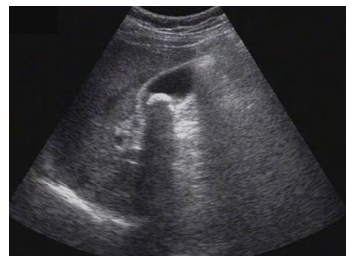

试题3:患者女性,50岁,间断上腹隐痛半年,诊断为(2分)

【答案】C

影像学3